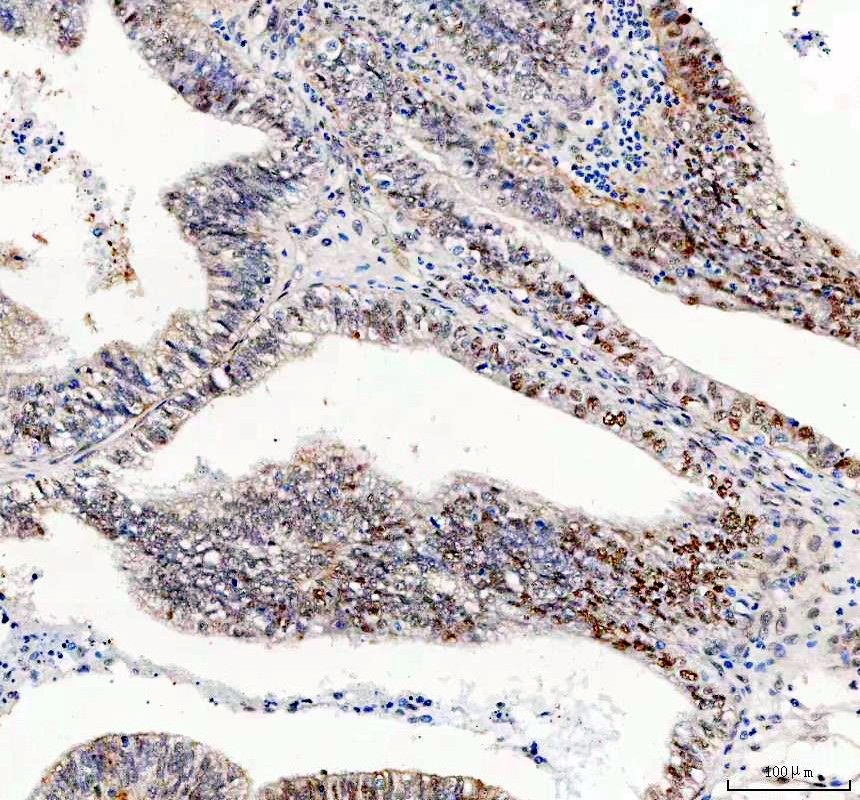

IHC analysis of GSK3B using anti-GSK3B antibody (A00791-3) .

GSK3B was detected in a paraffin-embedded section of human endometrial adenocarcinoma tissue. The tissue section was incubated with rabbit anti-GSK3B Antibody (A00791-3) at a dilution of 1:200 and developed using HRP Conjugated Rabbit IgG Super Vision Assay Kit (Catalog # SV0002) with DAB (Catalog # AR1027) as the chromogen.

IHC analysis of GSK3B using anti-GSK3B antibody (A00791-3) .

GSK3B was detected in a paraffin-embedded section of human endometrial adenocarcinoma tissue. The tissue section was incubated with rabbit anti-GSK3B Antibody (A00791-3) at a dilution of 1:200 and developed using HRP Conjugated Rabbit IgG Super Vision Assay Kit (Catalog # SV0002) with DAB (Catalog # AR1027) as the chromogen.